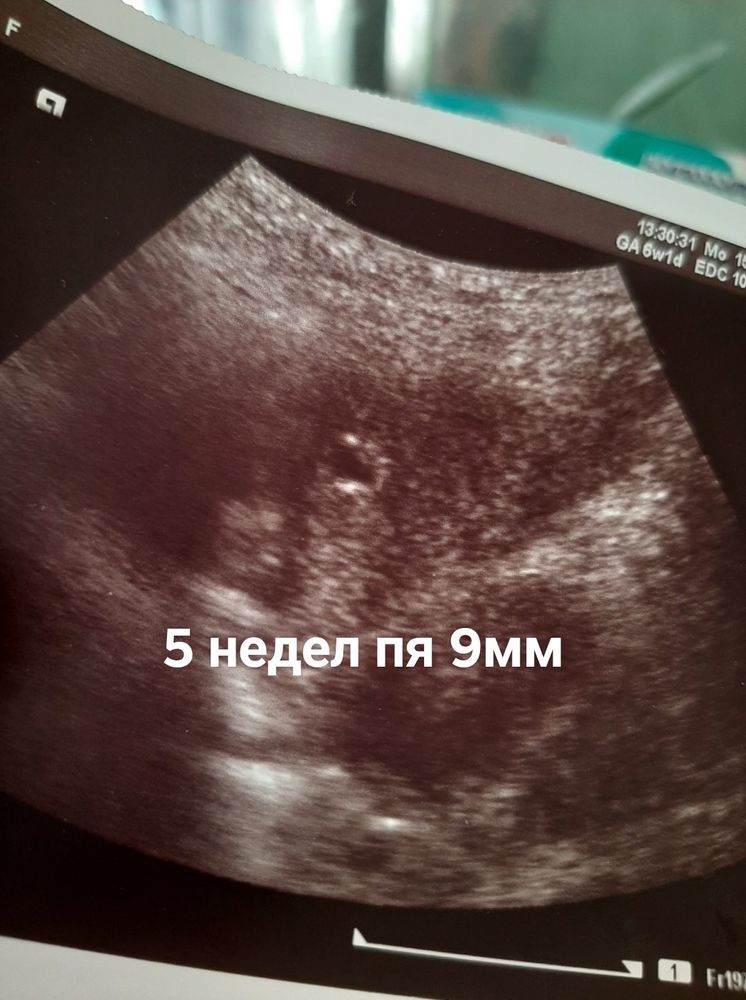

7недель динамика пя

Светлана , должна здать анализи в пониделник . Тест не делала. Меня уже на учёт поставили. Врач прописал таблетки чтоб снять тонус. Прочитала что у многих так было

Светлана , у меня в москве сестра она показала фото узи своему узисту она сказалв что тонус и думает что емриона тоже видно. После завтра иду на узи самаму лутшему узисту в грузие. Сечас принемаю утрожестан и магни б6.